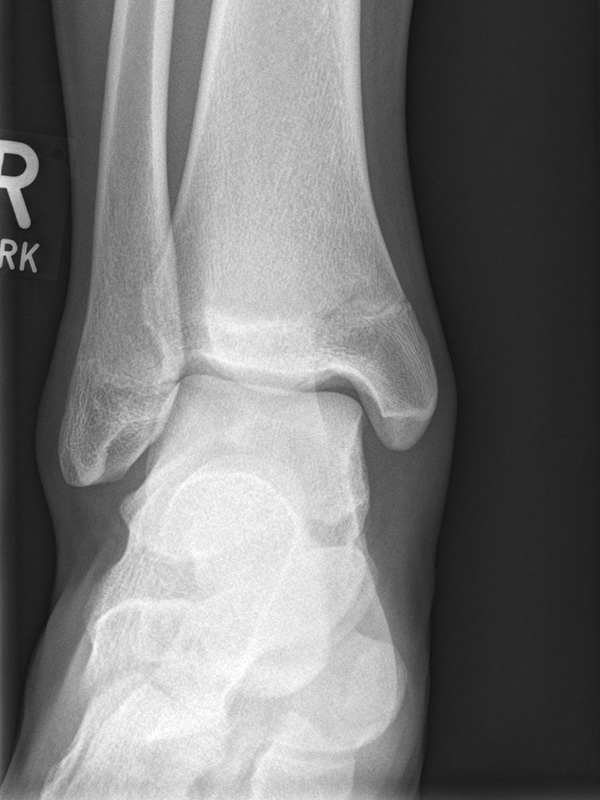

Sprunggelenk anterior-posterior (ap) ohne Belastung

Positionierung:

• Das Sprunggelenk befindet sich in 90° Stellung, das Bein ist gestreckt.

• Die Zehen sind direkt nach oben gerichtet.

• Der Zentralstrahl ist mittig auf den Gelenkspalt am oberen Sprunggelenk zentriert.

• Der Röntgenfilm liegt horizontal.

Kennzeichen des Röntgenbildes:

• Der Talus ist leicht außenrotiert.

• Der talofibulare Gelenkspalt wird partiell durch die distale Fibula überdeckt.

• Das anteriore Tuberkel der Tibia überlappt die distale Fibula.

Besondere Bemerkungen zum Beispielbild:

• Innenknöchelfraktur bei einem Jugendlichen.

• Keine relevante Dislokation.

• Die Wachstumsfugen sind noch erkennbar, im Wesentlichen aber geschlossen.